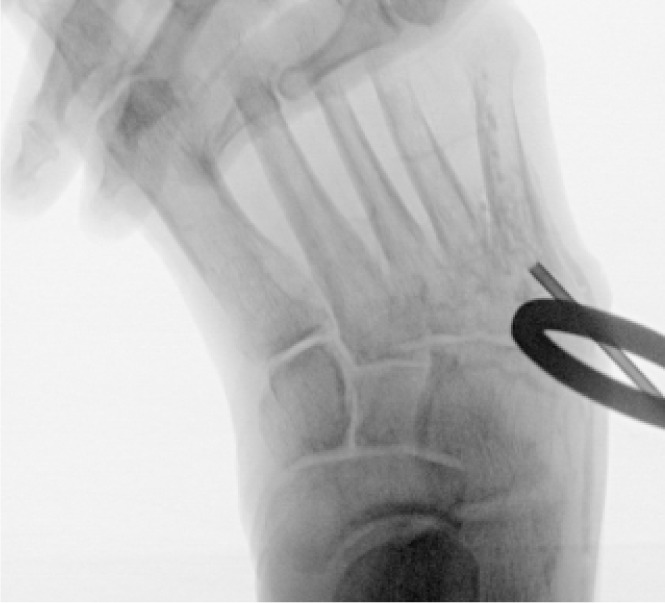

A staged surgical approach was implemented to address both the infectious and structural components contributing to the chronic ulcer. In the first stage, the patient underwent curettage and limited resection of the infected fifth metatarsal head. After thorough debridement, a bioabsorbable antibiotic-sulfate bone void filler was placed into the osseous defect to promote local antimicrobial activity and reduce dead space (Figure 10). This procedure was performed in conjunction with aggressive offloading and wound care to support granulation and early epithelialization.

FIGURE 10 Intraoperative image showing placement of antibiotic-impregnated bone void filler into the lateral metatarsal defect.